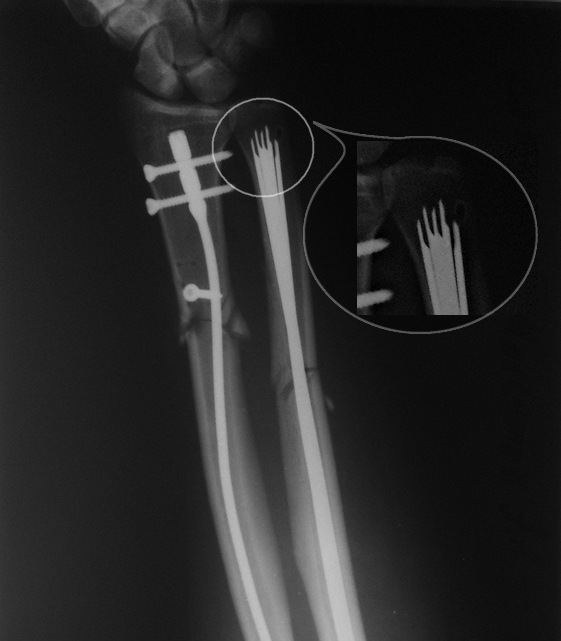

Мы бы выполнили интрамедуллярную фиксацию. Расчет на малоинвазивность при

наличии раны. Даже учитывая деформацию, введение гибкого стержня в radius

через Lister tub. не составит технических сложностей. Правда, наружный

аппарат мы бы наложили из деталей аппарата Илизарова как на рис. 1.

Фиксацию ulna пучком спиц через локтевой отросток. Идея - зафиксировать

малый фрагмент множеством спиц, тем самым исключив подвижность. Канал

видимо широкий, можно провести 4-5-6 спиц. "Ёжик", думаю удержит даже

порозный отломок.

Имя     : рис. 1.jpg

Тип     : image/jpeg

Размер  : 154574 байтов

Описание: отсутствует

Url     : http://weborto.net:8080/pipermail/ortho/attachments/20130302/71775e34/attachment-0005.jpg